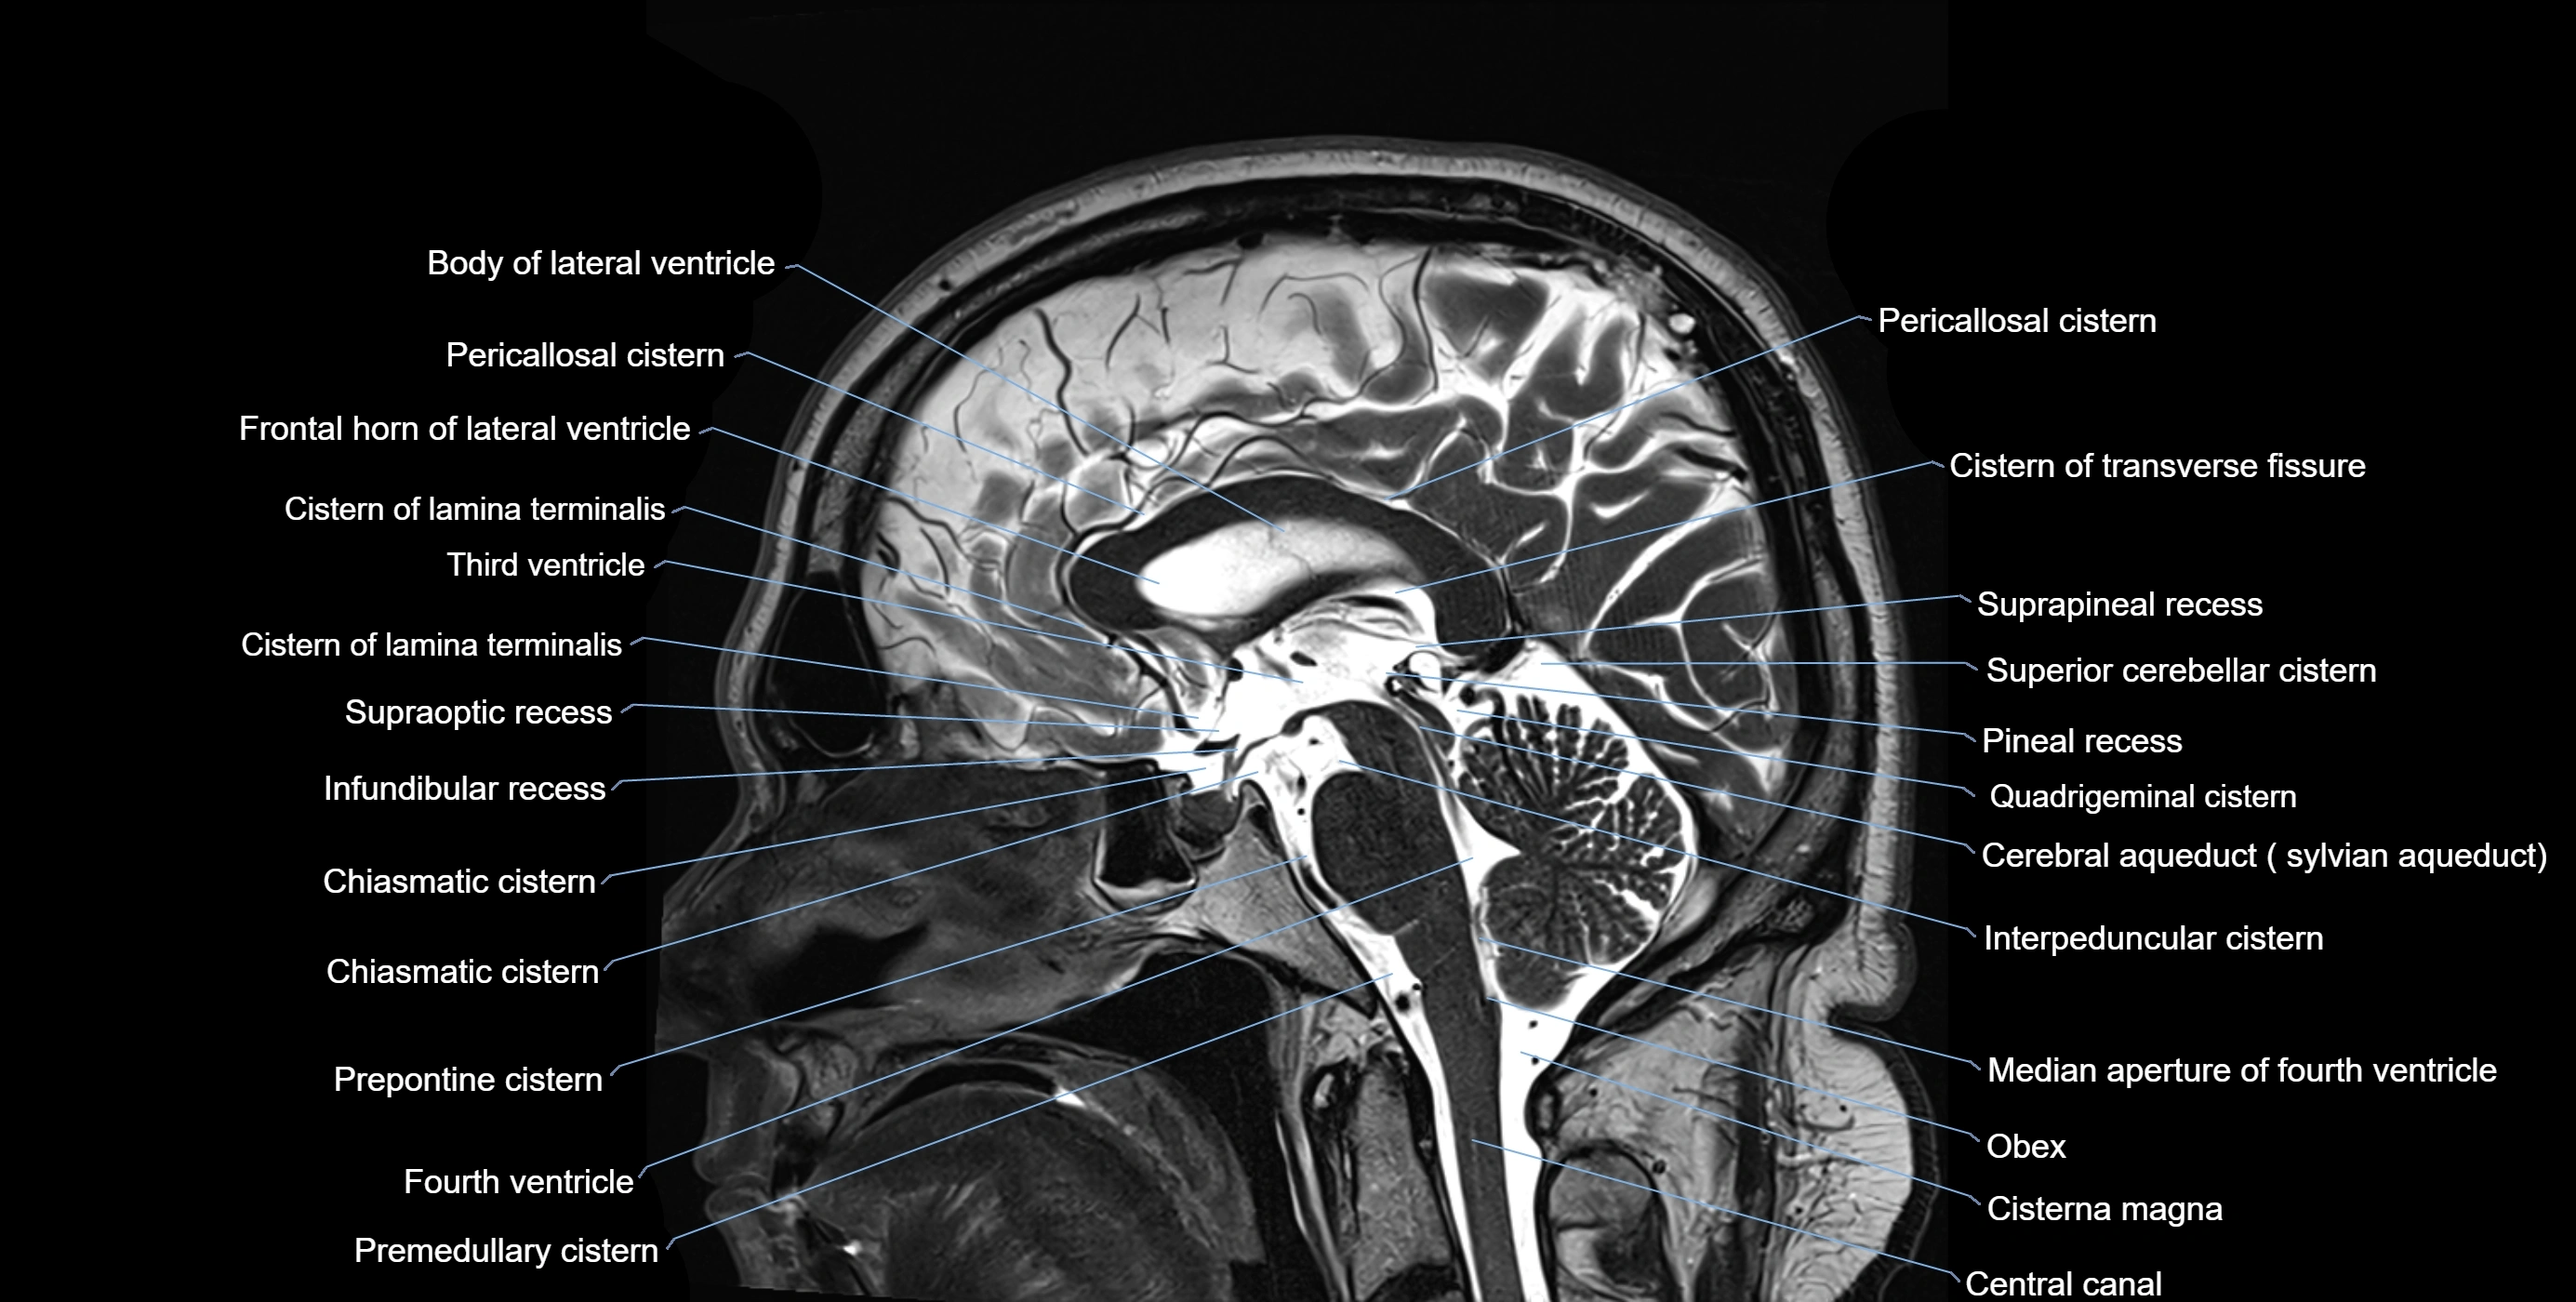

MRI images

image